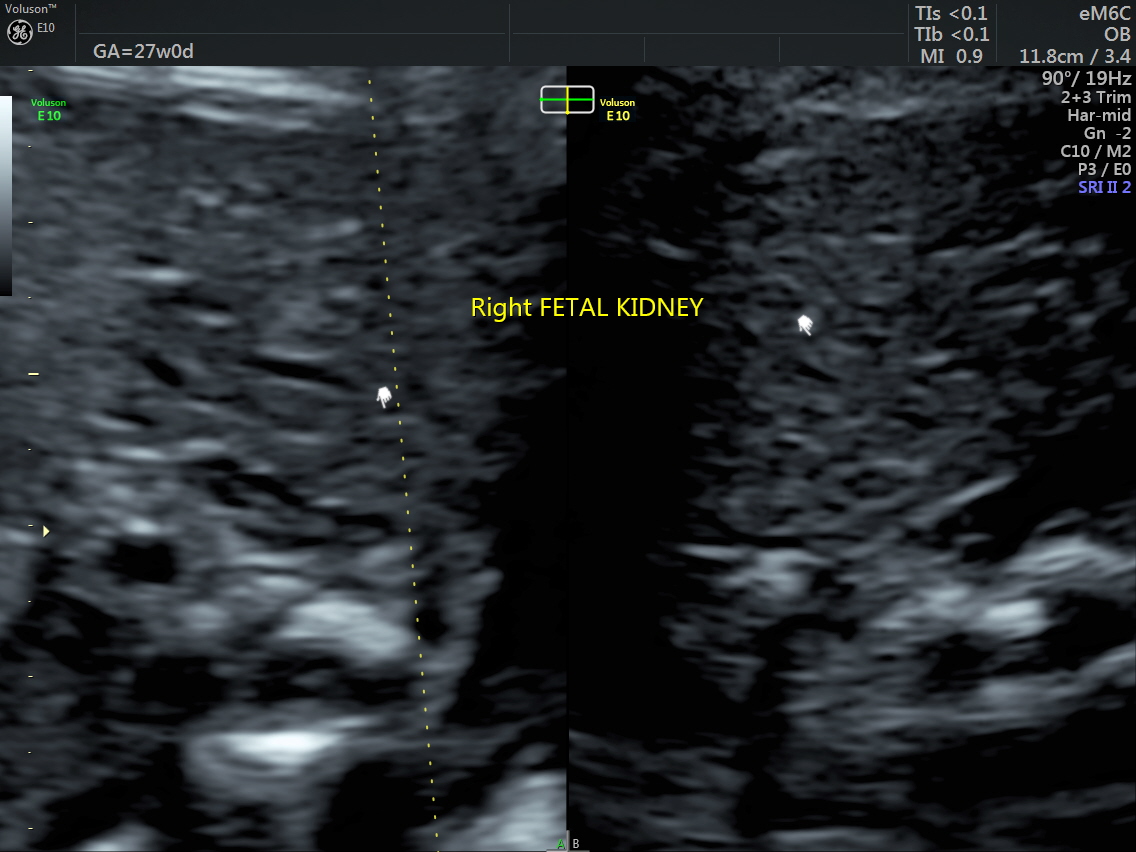

RT AORTIC ARCH_25 Published June 17, 2016 at 1136 × 852 in Rt aortic arch and aberrant left subclavian artery ← Previous Next →